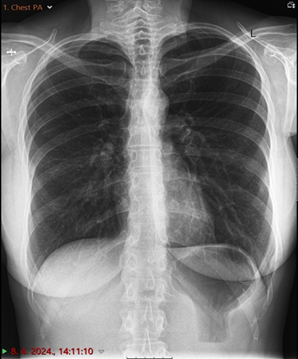

The chest X-ray posteroanterior (PA) and oblique radiograph

projection view

showed in the lateral part of the left sixth and

ninth rib, visible fractures without

major displacement of the bone fragments. There are no signs of pneumothorax.

Lung parenchyma and bronchial wall thickness were normal (Figure 1).

Figure 1. (A) Radiological image of the thorax. Chest oblique and

posteroanterior radiograph projection view

(B). The blue arrow points an visible fractures of the left sixth and ninth

ribs.